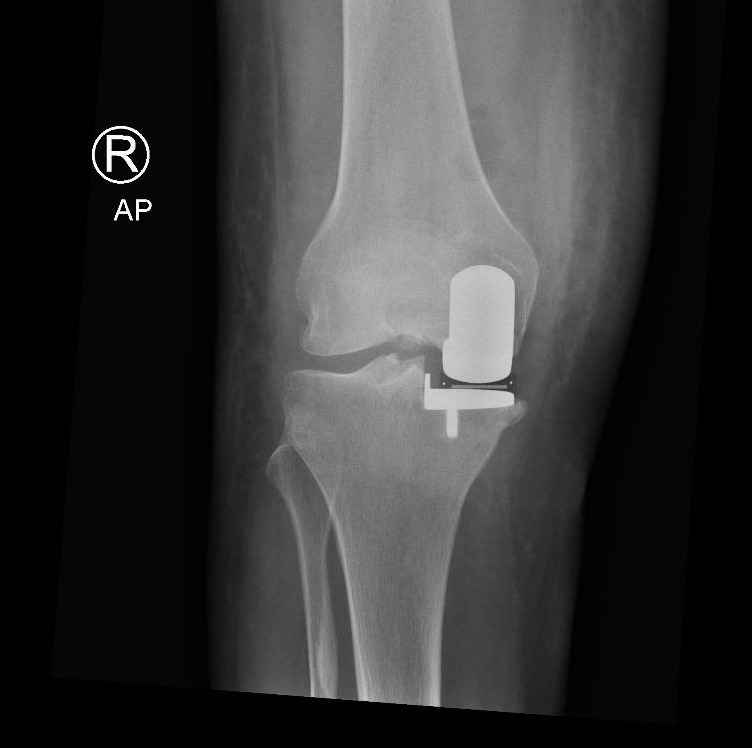

Often only one compartment (medial, lateral, patella) of the knee wears out and the remaining cartilage and ligaments in the other compartments are preserved and in a good condition. In this situation a partial (unicompartmental) knee replacement is indicated.

A partial knee replacement:

- Preserves ligaments within the knee – this confers better functional results following surgery

- Preserves bone for any future surgery

- Less traumatic - allows for a quicker recovery and reduced inpatient admission

Through a minimally invasive incision the inner compartment of the knee is replaced with a mobile bearing prosthesis. This consists of a metal femoral and tibial component with a polyethelene (plastic) insert that moves as the knee bends. The cruciate ligaments are preserved so the knee will feel ‘more normal’ thus providing improved functional results following surgery.